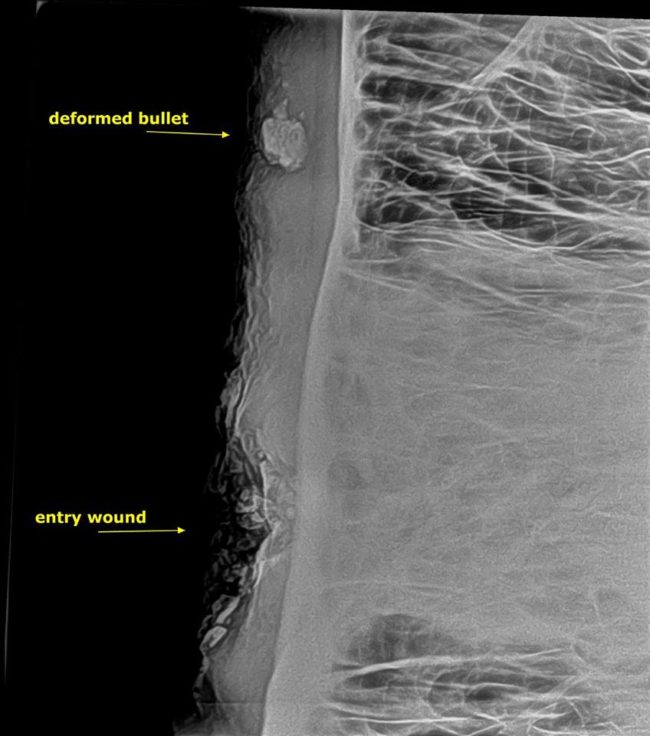

They performed an x-ray on his skull and found that a deformed bullet had fractured his sinuses, which was causing the pus.